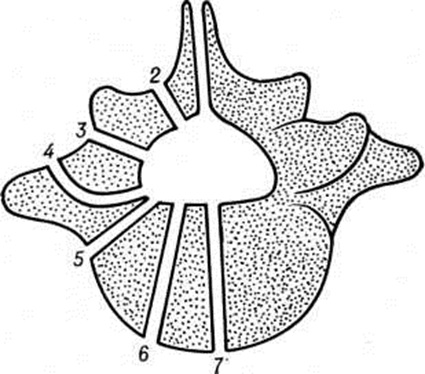

Локализация расщелины в теле или дуге позвонка может быть самой различной (рисунок 2). Рентгенологически легче распознаются расщелины, ориентированные в сагиттальной плоскости, которые лучше видны на рентгенограмме в прямой проекции. Расщелины в боковых отделах дуг и тел видны на рентгенограммах в боковой проекции, а иногда только на томограммах. При локализации в телах позвонков (spina bifida anterior) щель делит тело позвонка на две части, каждая из которых имеет на рентгенограмме в прямой проекции клиновидную форму. Чаще обе части тела позвонка расположены симметрично, напоминают по виду крылья бабочки — так называемый бабочковидный позвонок. Однако клиновидные части тела позвонка могут быть и асимметричными (рисунок 3). В процессе роста тела соседних позвонков приспосабливаются к форме аномальных позвонков.

Чаще встречаются дефекты в дугах позвонков, особенно нижних поясничных и крестцовых. Наиболее типично незаращение дуги по средней линии с расщеплением и недоразвитием, а иногда и отсутствием остистого отростка. Эта локализация Спина бифида легко выявляется на рентгенограмме в прямой проекции (рисунок 4). Реже расщелина локализуется в дуге между суставными отростками с одной или с обеих сторон — спондилолиз (рисунок 5). Диагностика Спина бифида этой локализации сложна, если она не сочетается со спондилолистезом (смотри полный свод знаний). При подозрении на спондилолиз обязательна рентгенография в двух проекциях, а при недостаточной информативности рентгенограмм необходимо томографическое исследование в боковой проекции (смотри полный свод знаний: Томография).